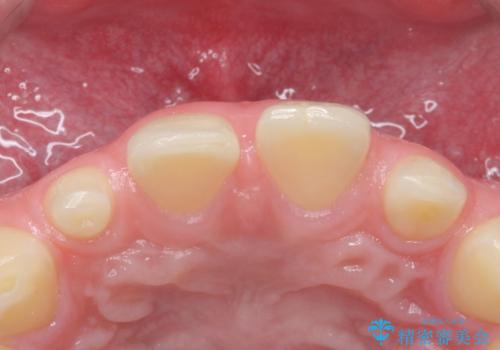

- 前歯の隙間を埋めたいとのことで来院された患者様です。

矯正治療とかぶせ物での治療どちらともご提案したところ、かぶせ物での治療をご希望されたためクラウンでの審美性回復を試みることとなりました。

今回のように、元の歯が小さすぎる場合は矯正治療での審美性回復が難しいことがあります。

形のイメージを反映させた仮歯を調整し、技工士さんと連携して製作したため口元に調和した非常に審美的なクラウンを装着することができました。